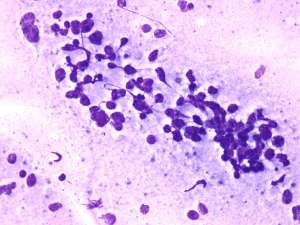

Cytology: suspicion of non Hodgkin lymphoma.

Biopsy was performed from the lesion and histopathology revealed large B cell lymphoma.

The cytological picture was identical with a small cell malignant tumor. Differential diagnostics included a metastatic small cell lung tumor and malignant lymphoma. The clinical presentation substantially decreased the likelihood of the former.